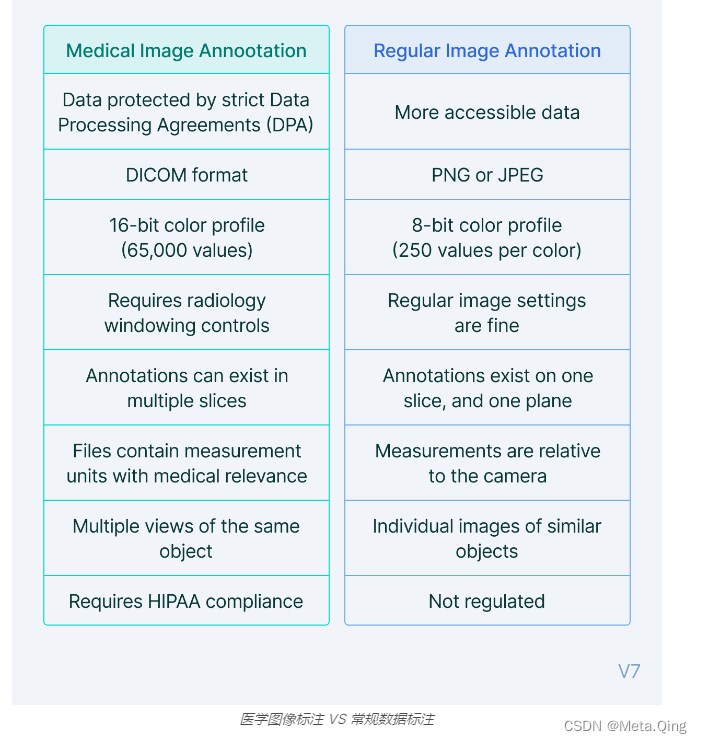

医学图像标注 VS 常规数据标注

如果您的最终目标是训练机器学习模型,那么注释医学图像与常规 PNG 或 JPEG 之间存在一些差异。

以下是一些不适用于其他视觉数据的医学成像方面需要考虑的事项。

让我们更详细地探讨其中的一些。